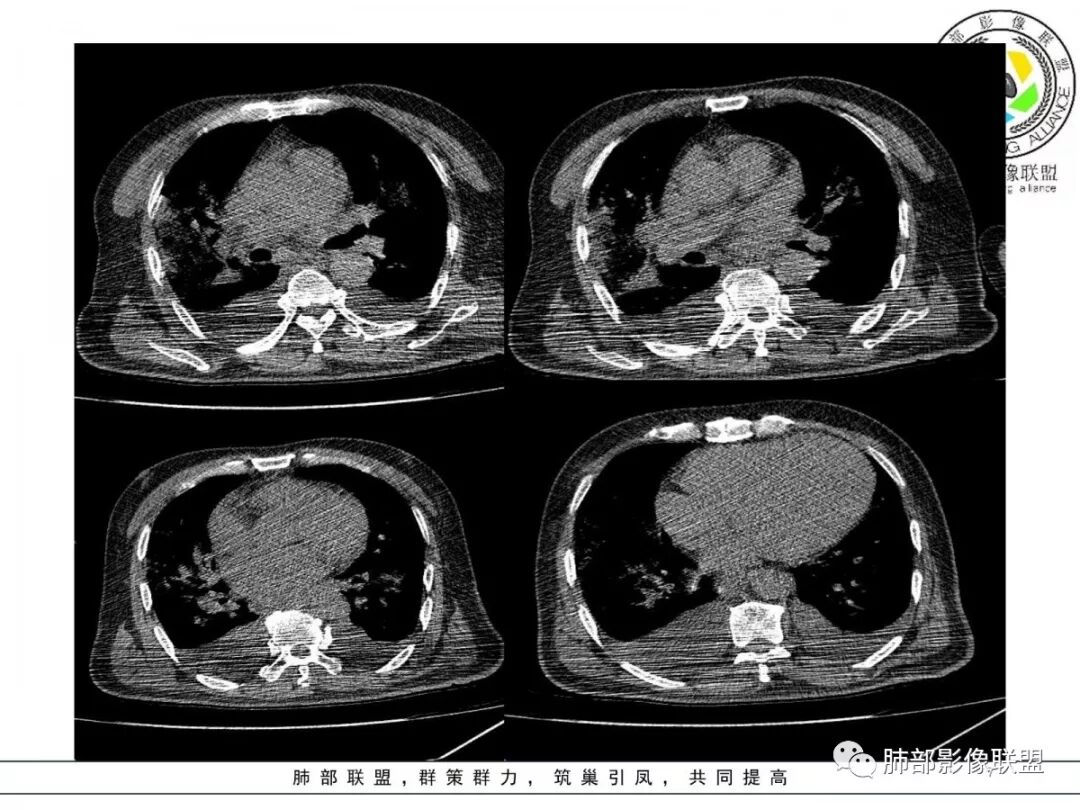

双肺以肺门为中心分布为主多发片状影,边缘模糊,部分小叶间隔有增厚,双侧胸腔积液,心影增大,考虑心衰、肺水肿。

老年男性,突发胸闷憋喘。蝶翼征、套袖征、肺静脉增粗、小叶间隔增厚,胸腔积液,心脏增大,符合心衰肺水肿,常规治疗后复查除外合并其它。

双肺弥漫对称边缘模糊斑片影,右肺为著,肺门影增大,双侧胸腔积液,左心增大 ,肺水肿。鉴别真菌,真菌很少有胸腔积液,肺泡出血,临床没有咳血。

双肺大片渗出影,以肺门为主,支气管血管束明显增粗,心影增大,左心室明显增大,双侧胸腔积液。诊断心衰,鉴别病毒肺这个病人应该同时还有贫血。。

双肺以肺门为主,大片渗出模糊影,双侧胸腔积液,心影增大。诊断急性心功能不全,肺水肿。患者感冒后引起考虑感染后肺水肿

心脏大,呈蝶翼状改变,支持肺水肿

双肺多发片状影,蝶翼状分布,小叶间隔增厚,双侧胸腔积液,肺水肿?

双肺实变影,向心性重力分布,形似蝶羽状,左心增大,双侧胸腔积液,急性起病,考虑肺水肿、急性左心衰?

考虑心衰:双侧胸水、心影明显大、双侧肺门旁斑片样阴影,边缘不清伴小叶间隔增厚。

两肺大片状实变影,中内带为主,边缘稍模糊

周围大片GGO

小叶间隔增厚